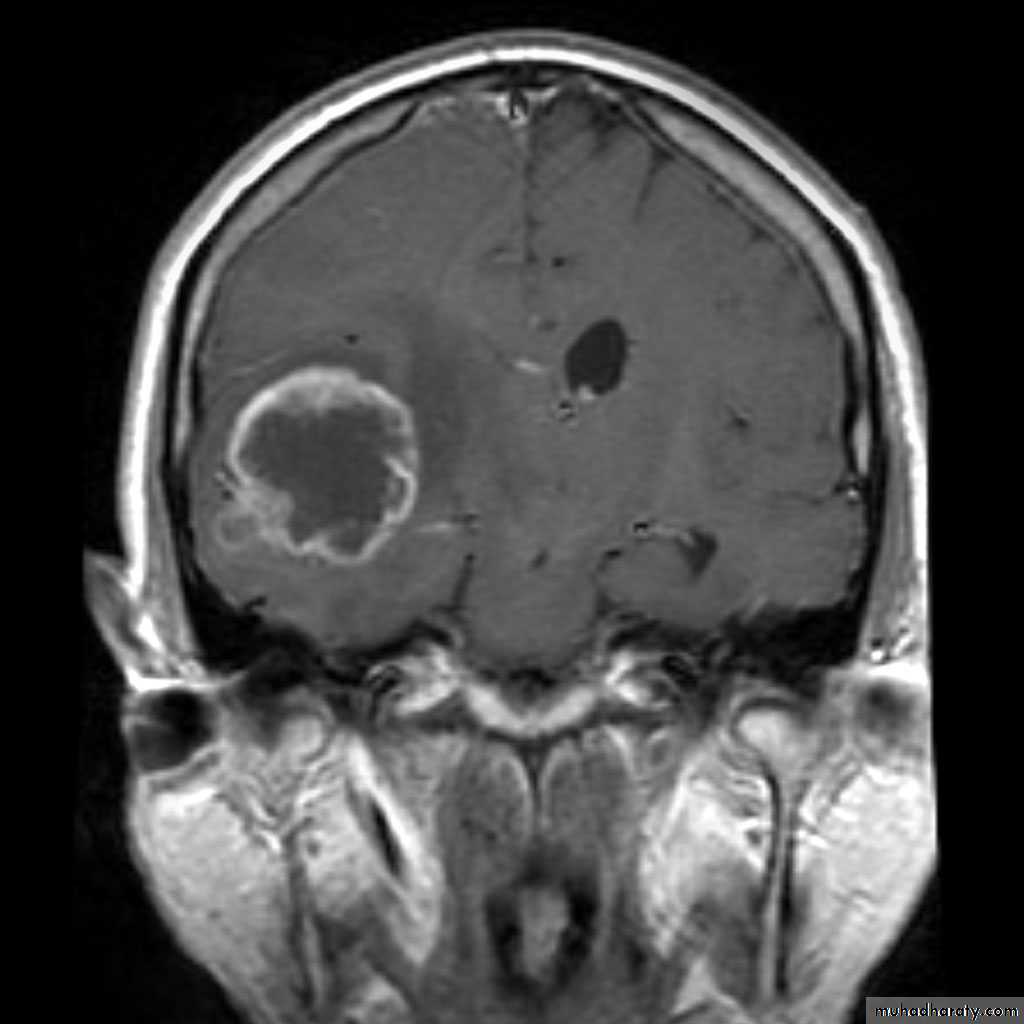

Glioma:• Typically appears as a solitary, irregular mass, surrounded by oedema

• Compression or displacement of the ventricles• The CT attenuation values of the tumour itself are usually low, but may be high or mixed.

• Partial enhancement with intravenous contrast medium, sometimes only the outer portion enhances, giving a so called ring enhancement pattern.

Brain metastasis

• Metastases in the brain may be of high, iso, or low density

• They usually show contrast enhancement (ring enhancement(

• They are often surrounded by significant oedema

• Metastases are typically multiple.